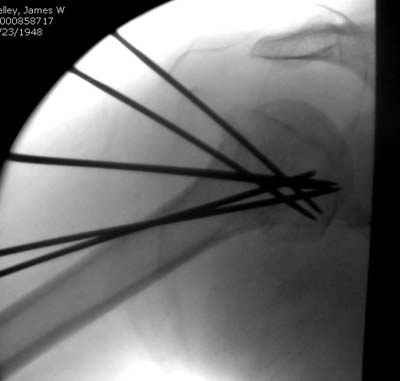

Спасибо за участие в дискуссии -перелом шейки плеча, для себя я прояснил многие технические моменты...

Посылаю послеоперационные Рг граммы.

Поздравляю, получилось просто замечательно. Если можно, расскажи чуть подробнее, как делали - как вправляли, как вводили спицы, поворачивали ли их?

Я и сам доволен результатом. В предпоследнем письме я кратко описал ход операции - закрыто репонировать не удалось( 2 недели с момента травмы и 1 неделя после неудачной репозиции) после удаления пучков спиц, пришлось сделать - 2см разрез на уровне перелома и с помощью периостального элеватора (золотое правило механики) *одеть* головку на дистальный отломок.

Спицы проводил через старые отверстия, вращая пучок импактором- направителем при его введении в головку.